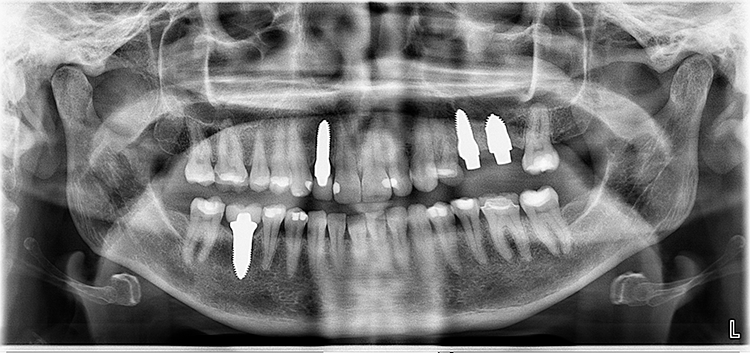

Abb. 2: Repräsentativer Fall von ABH Grad B Septus Typ II. a) Ansichten vor der Installation. Röntgenaufnahme der periapikalen Läsion an einem wurzelkanalbehandelten Molaren und klinische Ansicht der Typ-II-Socket nach der Extraktion. b) Die Ansichten nach der Installation zeigen das Implantat innerhalb des interradikulären Septums und das über dem Implantat platzierte A-PRF. c) Nachuntersuchungen nach 10 Tagen bzw. 2,1 Monaten. Die Röntgenaufnahme zeigt die Knochenbildung zwischen der Sinusmembran und dem apikalen Teil des Implantats. d) Jüngste Nachuntersuchung nach Einsetzen der Prothese.

Abb. 3: Repräsentativer Fall von Grad A Typ I. a) Präoperative Ansicht. Röntgenbild der periapikalen Läsion an einem wurzelkanalbehandelten Molaren. Die Höhe des Alveolarknochens zeigt Grad A an. b) Klinische und radiographische Ansicht der Implantatinsertion unter Verwendung einer Einheilscheibe mit großem Durchmesser (6×8 mm). A-PRF wurde um das Implantat und unter der Scheibe platziert. c) Nachuntersuchung nach 5,9 Monaten vor und nach der Zementierung und Aufbereitung. d) Jüngste Nachuntersuchung nach Einsetzen der Prothese

Abb. 4: Repräsentativer Fall von Grad A Typ III. a) Ansichten vor der Implantation. Röntgenbild der periapikalen Läsion an einem wurzelkanalbehandelten Molaren. b) Die Extraktionsalveole zeigt ein interradikuläres Septum vom Typ III (B).

Der Erfolg der Implantate wurde nach den Kriterien des Pisa-Konsensus von 2008 bewertet [9]. Alle Implantate wurden als Gruppe I mit einem durchschnittlichen marginalen Knochenverlust von –0,1775 + 0,68 mm nach 1 Jahr Implantation eingestuft, die einen Knochenverlust von < 2 mm und keine Empfindlichkeit, Beweglichkeit oder Exsudat aufwiesen.

Querschnittsbilder aus dem DVT zeigen eine hohe Genauigkeit und Zuverlässigkeit bei linearen Knochenmessungen im Zusammenhang mit der Implantatbehandlung [2]. Marginale Knochenniveaus wurden am Schnittpunkt zwischen der Längsachse des Implantats und der mesiodistalen Linie gemessen, die durch den größten krestalen Knochen auf jeder Seite des Implantats markiert ist und als Referenzpunkt für die Messung des Knochenverlusts bei Nachuntersuchungen dient. Trotz der begrenzten Anzahl von Implantaten und der Beschränkungen der Studie wurde eine Überlebensrate von 100% erreicht.